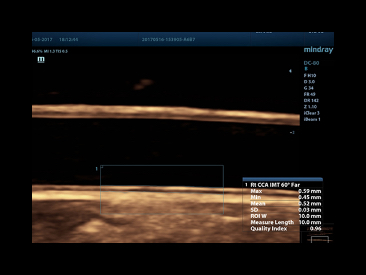

Auto IMT

Automatically detect and calculate IMT for cardiovascular risk assessment.